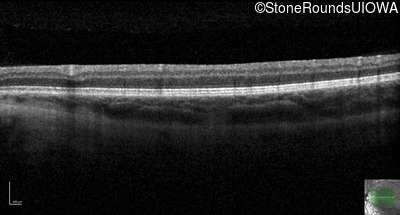

Age at visit: 29 years

This 29 year old woman was first found to have reduced acuity at age 5 when her parents noticed her sitting very close to the TV and holding books very close to her face to read. She does not think her vision has changed appreciably since she was 5. When she was 6 years old she was able to see 9 out of 14 color plates.